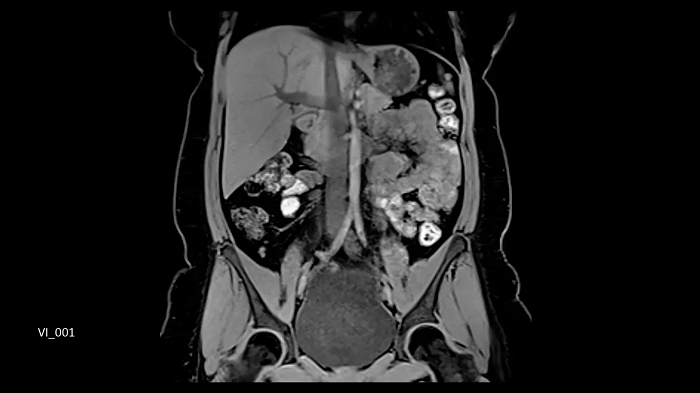

3D T1 CAIPIRINHA VIBE Dixon

1 station

50 cm z-FOV

Full abdominal coverage from the liver dome to the pelvis enables comprehensive oncological scans in a single station with outstanding quality.

- Body 18

- BioMatrix Spine 72

Image Credit: Siemens Healthineers